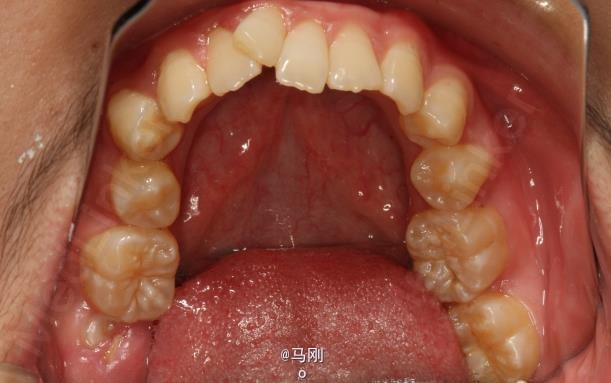

随访 讨论

效果很好。